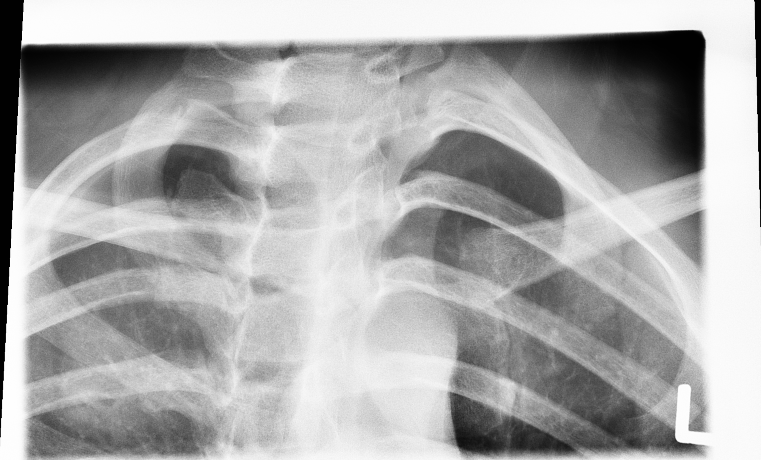

| 28 |

Abnormal ll col |

Abnormal Left upper lobe lung nodule |

Please check |

Correct |